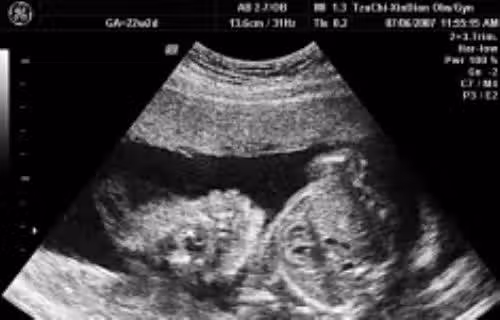

高二的女兒「不小心懷孕」,而且因為藏肚看不出來,直到8個月大才發現,但爸爸選擇不責備,親吐真心話「不敢讓妳知道爸爸心痛」😭😭 #最後處理方式讓人鼻酸

示意圖來源:噓星聞、媽媽經

但因為事情已經發生了,爸爸先是帶女兒到醫院做檢查,也發現孩子的爹是女兒的國中同學,雙方都是未成年,最後他選擇不責備,「罵了有什麼用?把事情解決才是當務之急。」之後兩方家長碰面,都同意讓兩人在一起,再去跟老師說明事情真相跟辦休學,還好校方也很幫忙以請事假處理,並同意用前2次段考平均成績當期末考,因老師認為女兒很乖巧很熱心,當然要給予幫助。